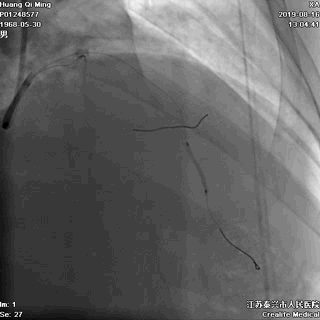

冠状动脉造影

右冠状动脉无严重狭窄

左主干前分叉处血管正常

LCX近中段病变,狭窄最重达90%

LAD中远段血管偏细,弥漫性病变,狭窄达90%

导丝通过病变

球囊扩张,PTCA